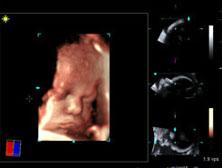

The volume imaging software offers a true stereoscopic view of 3-D images. Created in collaboration with NVIDIA Corp., the new technology creates a 3-D imaging experience that is designed to be more immersive, detailed and realistic than previous solutions. NVIDIA 3D Vision stereoscopic glasses and NVIDIA Quadro FX high-end professional graphics solutions render 3-D/4-D images of the fetus.

The clinical images, obtained with the ACUSON S2000 system, are further enhanced using Amnioscopic Rendering, a Siemens technology that uses NVIDIA 3D Vision technology, users can experience 3-D images in real 3-D. This enhancement is intended to provide additional information to the physician and assist in communication between surgeons and patients or aid in treatment or surgical planning.